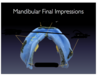

where should finger rests be for the custom tray

1st molar and 2nd premolar

how large should the handle of a custom tray be

9mm height

10 mm width